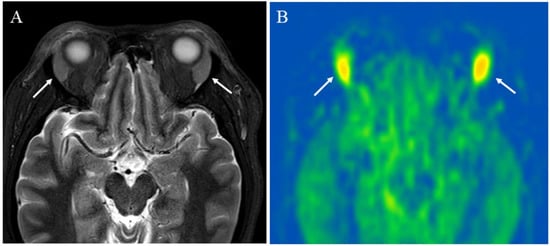

5.1.1. Inflammatory Lesions: Sialadenitis and Dacryoadenitis

- Takahashi, H.; Yamashita, H.; Morooka, M.; Kubota, K.; Takahashi, Y.; Kaneko, H.; Kano, T.; Mimori, A. The utility of FDG-PET/CT and other imaging techniques in the evaluation of IgG4-related disease. Jt. Bone Spine 2014, 81, 331–336. [Google Scholar] [CrossRef] [PubMed]

- Tsuji, S.; Iwamoto, N.; Horai, Y.; Fujikawa, K.; Fujita, Y.; Fukui, S.; Ideguchi, R.; Michitsuji, T.; Nishihata, S.; Okamoto, M.; et al. Comparison of the quantitative measurement of 18F-FDG PET/CT and histopathological findings in IgG4-related disease. Clin. Exp. Rheumatol. 2021, 39, 1338–1344. [Google Scholar] [CrossRef]